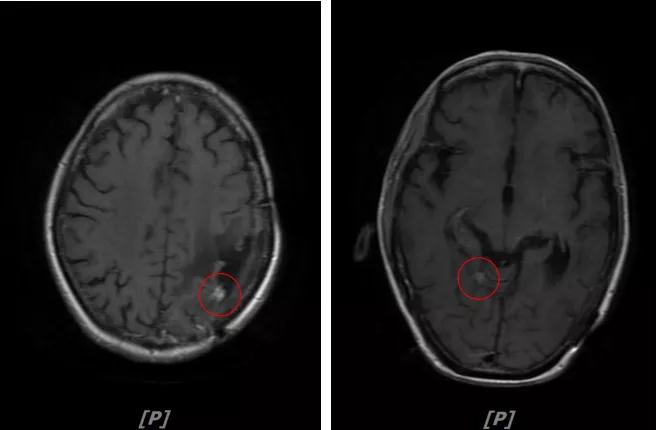

4.病情第3次进展:2018年10月患者头痛症状又加重

头颅增强MR:左侧顶颞叶见片状T1WI低信号、T2WI高信号影,病灶大部信号接近脑脊液;增强后可见左侧额叶、顶叶、两侧海马及右侧小脑半球呈多发斑点状、结节样明显强化,大者大小约14x11mm,较2016-12-11增强老片病灶增大、增多;两侧半卵圆区、侧脑室旁见较对称片状T1WI低信号、T2WI高信号影,增强后未见明显强化( 较2017-8-9MR老片稍明显) ;余脑室、脑池、脑沟大小形态可,中线结构居中无移位。左侧上颌窦粘膜轻度增厚

左顶颞叶转移瘤治疗后改变;脑内多发强化灶,考虑转移,较前增大增多

两侧脑室旁云絮状异常信号:考虑放疗后改变

患者二线治疗的PFS为22个月,2018年11月患者给予后续解救治疗为吡咯替尼(400mg/d)联合阿那曲唑;患者头痛症状好转,病灶继续缩小,继续定期复查。